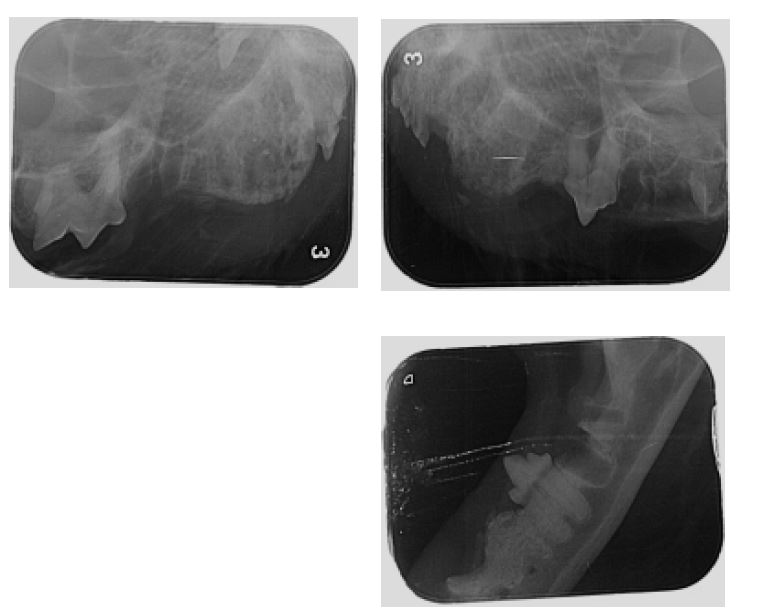

Ja, sie hat FORL - und sie hat absolut keine Symptome gezeigt. Ich hänge den Behandlungsbrief und die Röntgenbilder hier mal an.

Tja, diese Diagnose hat mich nun doch einigermaßen schockiert, muss ich sagen. Ich hätte Stein und Bein darauf geschworen, dass Hermine kein FORL hätte, weil sie absolut überhaupt keine Schmerzanzeichen gezeigt hat. Sie hat vollkommen normal gefressen, sie hat nie gespeichelt, nie den Kopf beim fressen schief gehalten und nie das Futter wieder aus dem Mäulchen fallen lassen. Und trotzdem waren zwei Wurzeln schon komplett weggefressen.

Anhänge

Befund.JPG

170,5 KB

· Aufrufe: 46

Röntgenstatus1.JPG

67,1 KB

Röntgenstatus2.JPG

43,4 KB

· Aufrufe: 40